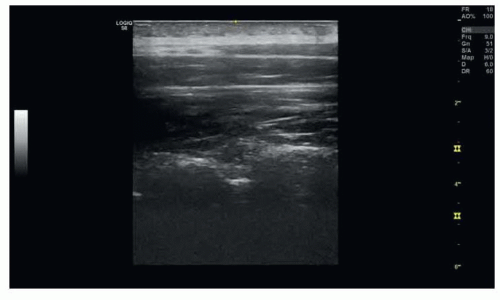

FIG 1 • Ultrasound of the lumbar and thoracic spine for epidural placement.